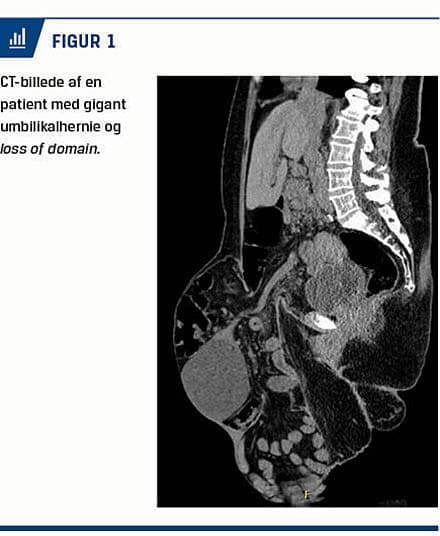

En 51-årig kvinde var i systemisk behandling med azathioprin for morbus Crohn. Igennem ti år havde hun haft et primært umbilikalhernie, som var tiltaget i størrelse. Grundet svær overvægt og dertilhørende risici ved kirurgi afstod man initialt fra at operere hende for umbilikalherniet. Ved CT fandt man, at herniedefekten målte 12 cm horisontalt og 8 cm vertikalt. Selve broksækken indeholdt det meste af tynd- og tyktarmen samt en benignt udseende ovariecyste, og patienten havde således udtalt loss of domain (Figur 1). Efter et påkrævet præoperativt vægttab fra 160 kg til 113 kg reduceredes patientens body mass index til 35 kg/m2, og en operation med præoperativ administration af BTA blev planlagt.